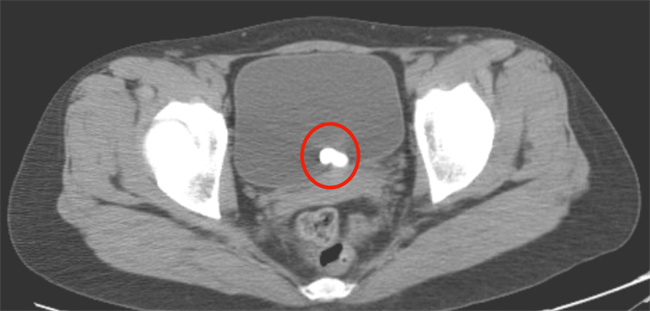

女性尿道旁囊肿,又称为Bartholin腺囊肿,是一种较为常见的妇科疾病。其主要原因是尿道旁腺出口被阻塞,导致腺内分泌物积聚形成囊肿。一些因素可能会导致Bartholin腺阻塞,如感染、损伤或其他疾病等。下面将介绍Bartholin腺囊肿的原因及护理方法。...

女性尿道旁囊肿,又称为Bartholin腺囊肿,是一种较为常见的妇科疾病。其主要原因是尿道旁腺出口被阻塞,导致腺内分泌物积聚形成囊肿。一些因素可能会导致Bartholin腺阻塞,如感染、损伤或其他疾病等。下面将介绍Bartholin腺囊肿的原因及护理方法。